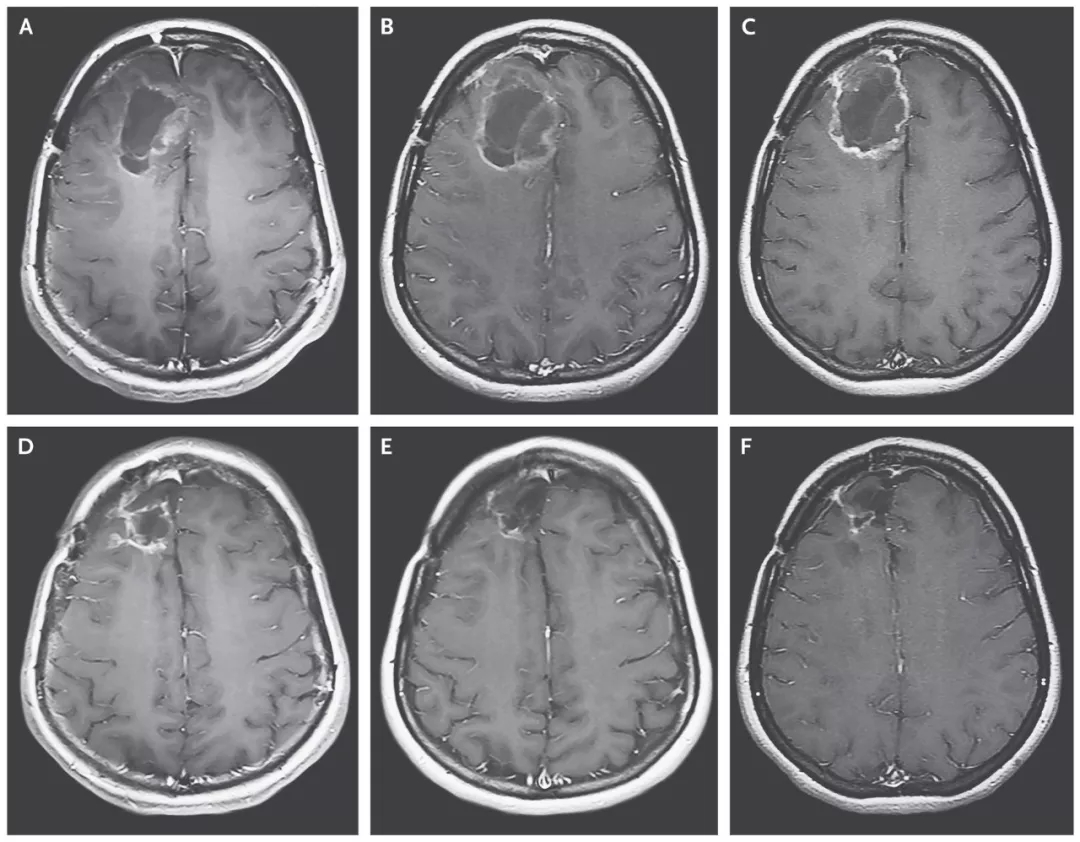

(患者脑部肿瘤的缩小清晰可见)

结果显示:治疗组的中位生存期是12.5个月,与11.3个月的历史数据相差无几;治疗组的2年生存率为21%,已比历史数据(14%)高出50%;3年生存率同样为21%,而历史数据仅为4%。经过溶瘤病毒的治疗,生存率猛增5倍!

20岁多岁的斯蒂芬妮·利普斯科姆是一名脑胶质母细胞瘤复发患者,被医生断言仅剩几个月的生命。幸运的是,她成为了首名接受这项试验性病毒治疗的患者。在接受治疗后,她大脑里的肿瘤不断缩小。在2014年,肿瘤竟彻底消失了。这个“奇迹”经美国CBS电视台知名栏目《60分钟》报道后,震惊全美。